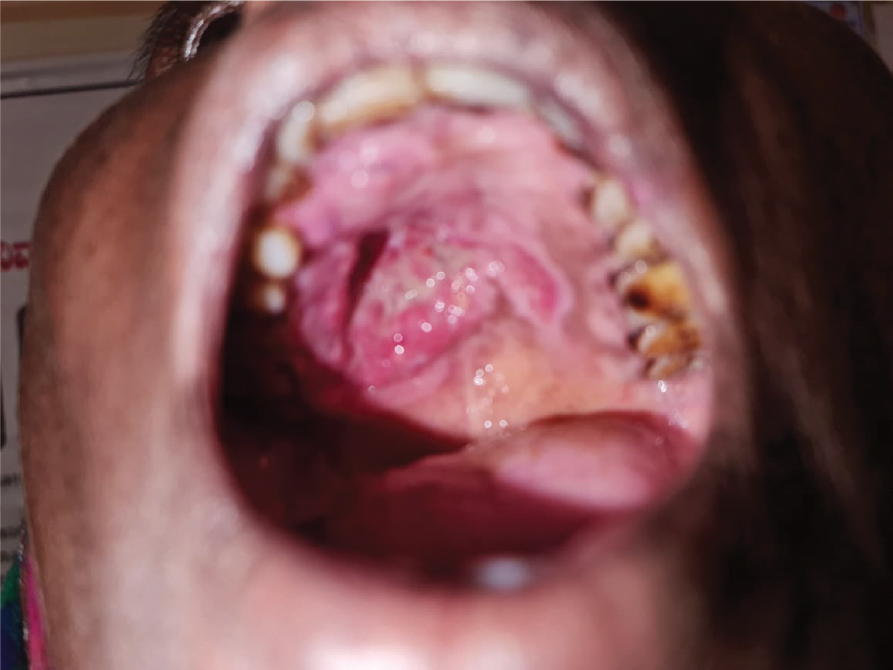

On examination, the growth measured 2.5 × 2.5 cm in size. It appeared smooth with no ulcerations or bleeding points, etc. thus ruling out a malignant growth (Fig. 1).

Figure 1. Hard palate growth.

On palpation, the swelling was unilocular, nontender, firm, immobile with a well-defined margin. The mucosa over the growth was stretched and lymph nodes of the neck appeared normal.